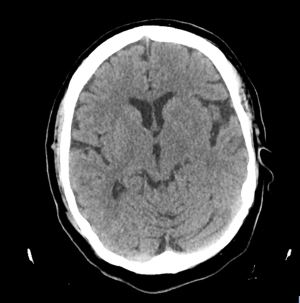

A las 72 horas aproximadamente se realiza una resonancia cerebral: